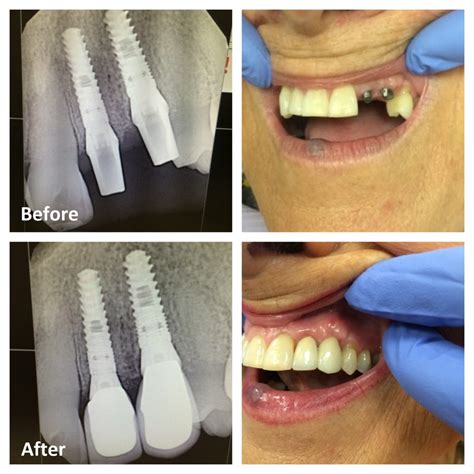

Losing a tooth in your smile line can be a deeply unsettling experience, impacting not only your ability to chew and speak clearly but also your self-confidence. When faced with this issue, many patients turn to front dental implants as the premier solution for restoring both form and function. Unlike traditional bridges or dentures, which sit on top of the gums, dental implants serve as a permanent replacement for the entire tooth structure, from the root to the crown. By mimicking the natural tooth’s anatomy, these implants offer unparalleled stability and a remarkably lifelike aesthetic that is essential for front-facing teeth.

The journey to restoring your smile with front dental implants is a multi-step process that requires careful planning. While the timeline can vary depending on your individual bone health, the general roadmap remains consistent for most patients.

Comprehensive Exam Digital imaging (CBCT scans) to assess bone density and nerve positioning.

Implant Placement Surgical insertion of the titanium post into the jawbone.

Osseointegration A healing period of 3–6 months where the bone fuses to the implant.

Abutment & Crown Attaching the connector and the final, custom-made ceramic crown.

Advances in digital dentistry have revolutionized how front dental implants are placed. Today, dentists utilize guided implant surgery, which uses 3D models of your jaw to map out the exact position, angle, and depth of the implant before the procedure even begins. This level of precision minimizes surgical trauma and drastically improves the aesthetic result. By choosing a provider who utilizes these digital tools, you are ensuring the highest possible level of care for your smile.